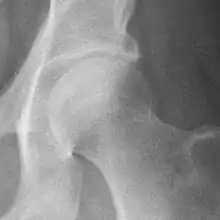

The most commonly used radiographic classification system for osteoarthritis of the hip joint is the Kellgren–Lawrence system (or KL system).[6] It uses plain radiographs.

| Grade | Description |

|---|---|

| 0 | No radiographic features of osteoarthritis |

| 1 | Possible joint space narrowing (normal joint space is at least 2 mm at the superior acetabulum)[7] and osteophyte formation |

| 2 | Definite osteophyte formation with possible joint space narrowing |

| 3 | Multiple osteophytes, definite joint space narrowing, sclerosis and possible bony deformity |

| 4 | Large osteophytes, marked joint space narrowing, severe sclerosis and definite bony deformity |